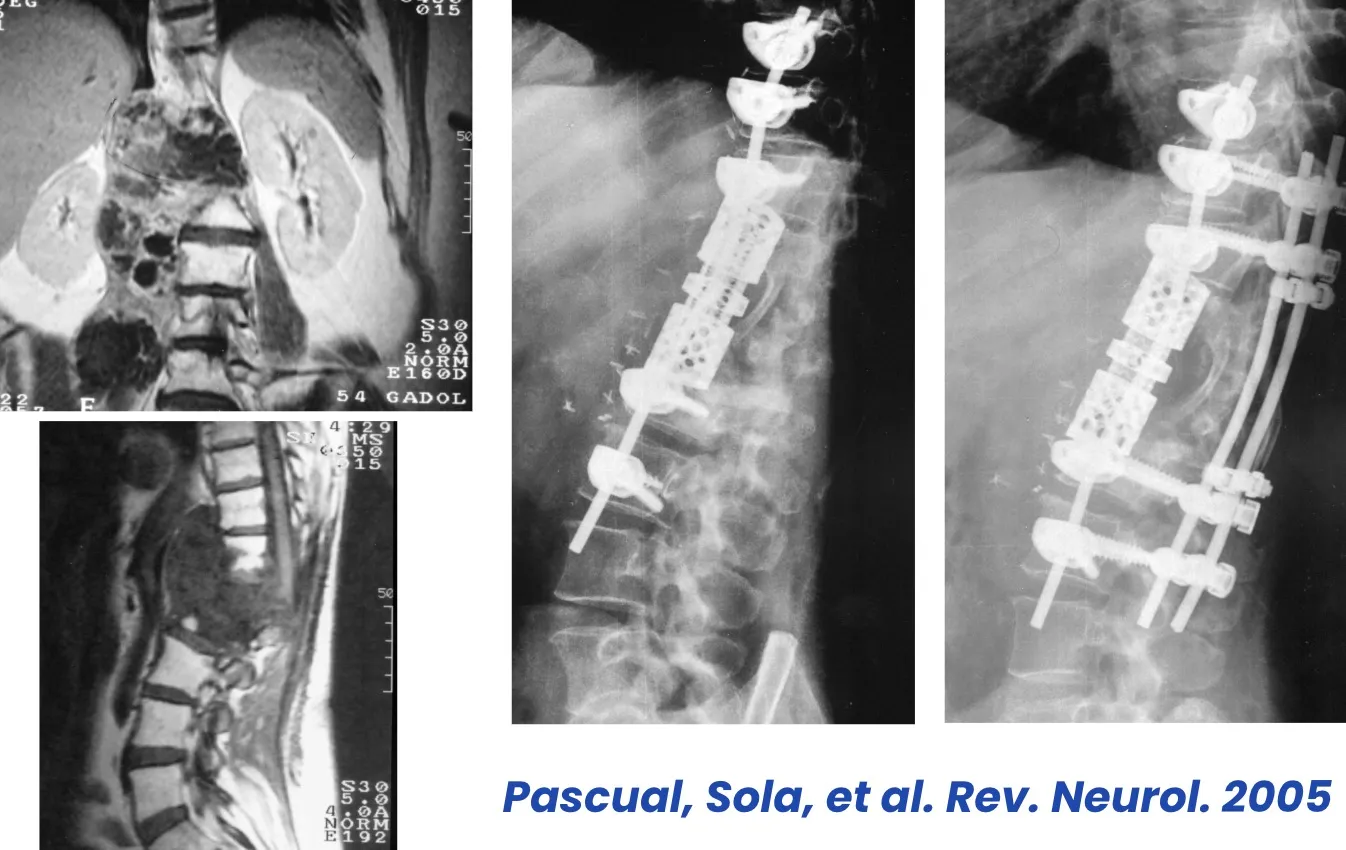

Este es un ejemplo de las intervenciones de gran envergadura que en ocasiones es necesario realizar, como en el caso de las cirugías de la región sacra, donde la complejidad anatómica y la proximidad de estructuras vitales exigen una planificación meticulosa y un abordaje multidisciplinario.

Gilbert et al., 1978 ·

Sola et al., 1983 ·

Benzel, 2005